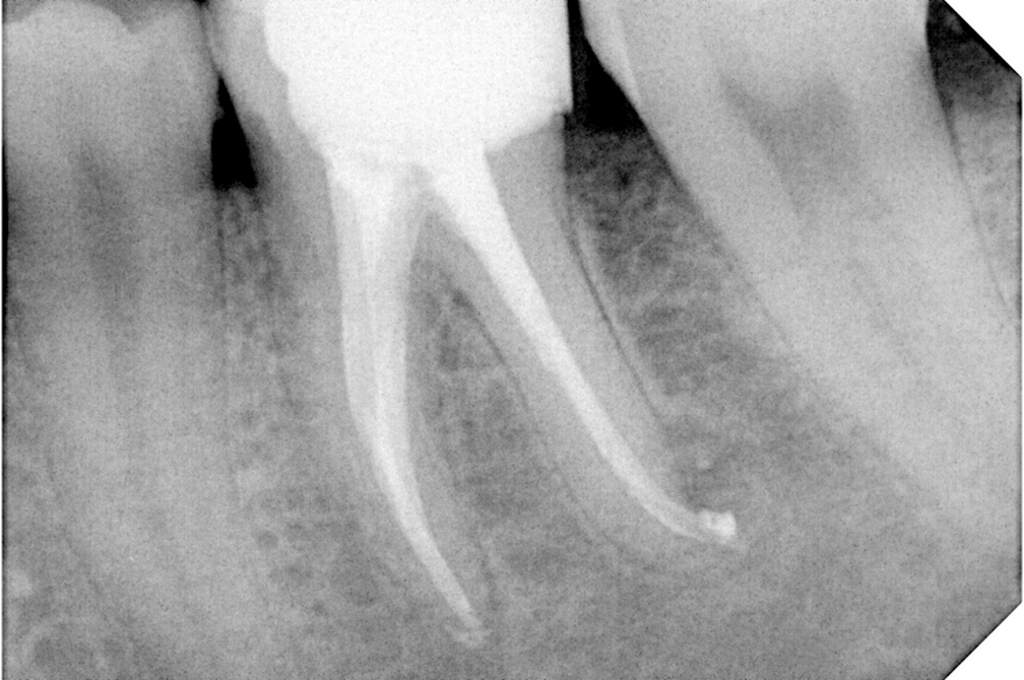

Χρόνια φλεγμονώδης περιακρορριζική βλάβη, κυρίως,

λόγω ενδοδοντικής αιτιολογίας. Μετά την ενδοδοντική θεραπεία

ακολούθησε περιοδοντική θεραπεία.

Δύο χρόνια μετά, παρατηρείται πλήρης εξαφάνιση της βλάβης.